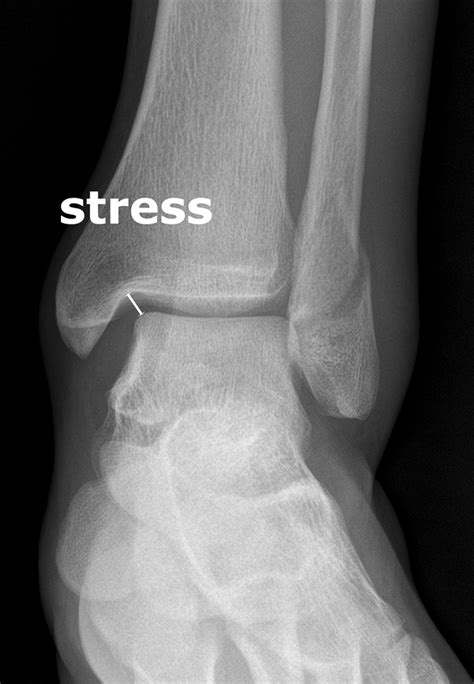

The fibula is the thin, long bone located on the lateral (outer) side of the lower leg. While it does not bear the majority of your body weight—the tibia carries most of it—the fibula serves as a crucial anchor point for various muscles that control ankle stability and foot movement. A Fibula Stress Fracture occurs when the bone is subjected to repeated force faster than it can remodel and repair itself. Over time, these tiny, microscopic cracks accumulate, leading to structural weakness.

• Point tenderness, where the pain is centralized in one specific spot along the fibula bone.

If you find that the pain persists for more than two weeks despite taking rest days, it is highly recommended to seek a professional medical evaluation, such as an X-ray or MRI, to confirm the diagnosis.